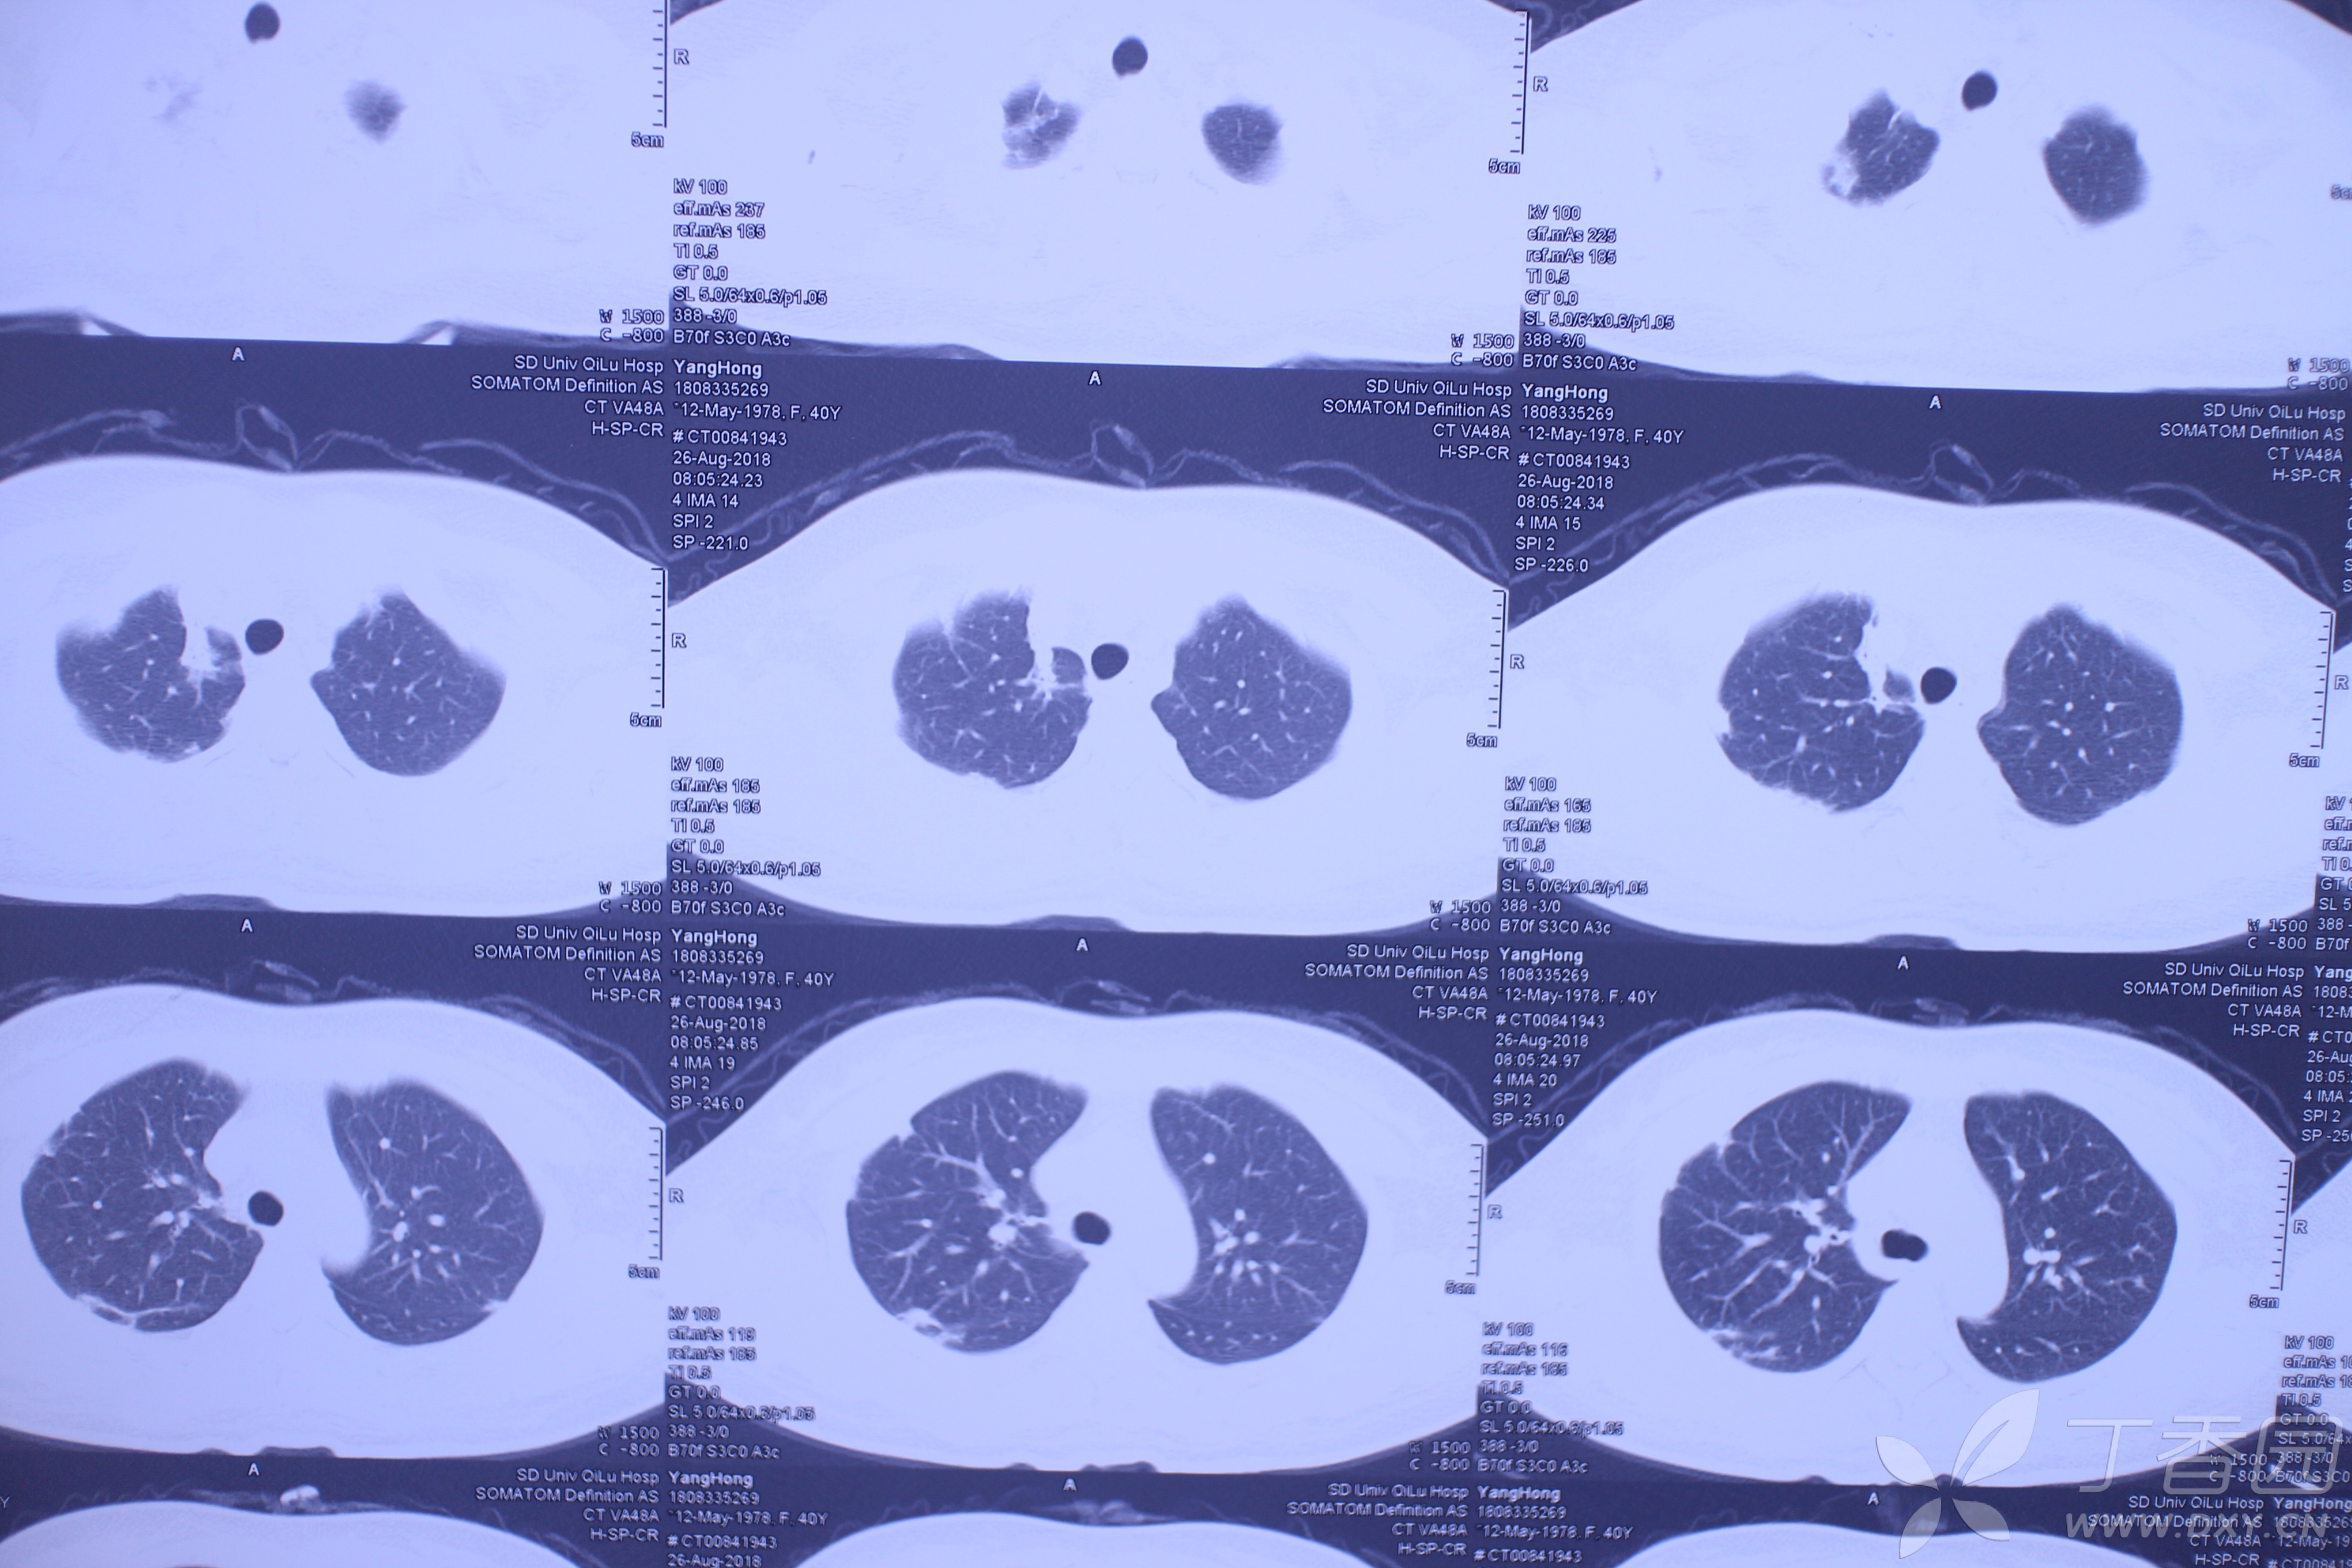

百草枯肺部损伤的特点不会导致进行性肺纤维化病例帖

图片尺寸3456x2304